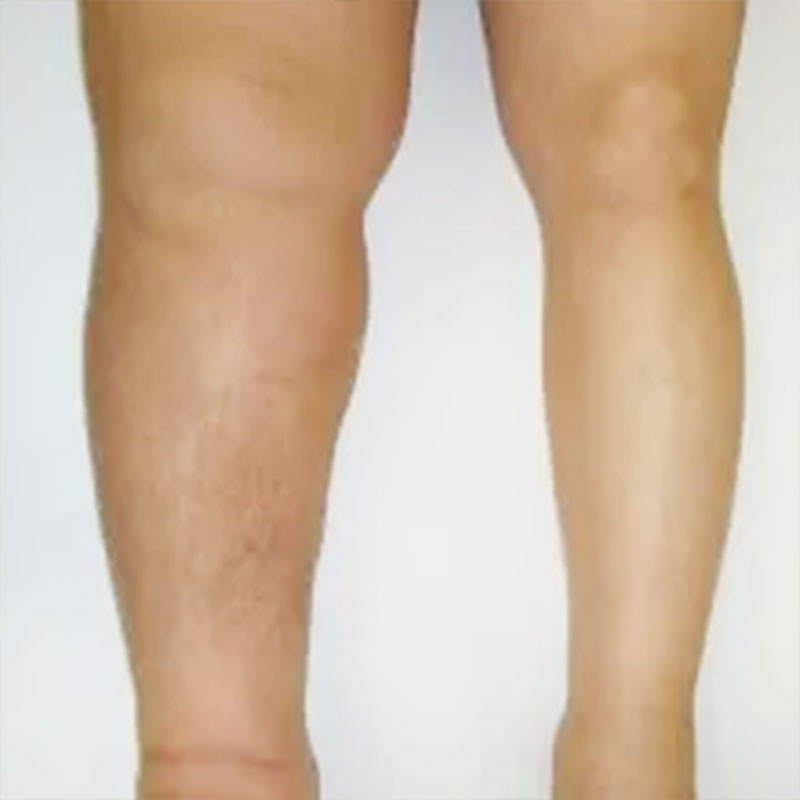

リンパ浮腫は手や足にむくみの症状が現れるケースが多いのですが、顔面や胸腹部をはじめ、全身のどの部位にも発症する可能性があります。

リンパには体液区分線が存在するため手術を受けた部位によって発症する場所が変わり、乳がんの手術後は手術側の腕、骨盤内の手術後ではどちらかの足、または両足に発症します。

放置することで進行することが多いとは言えますが個人差が大きく、発症後数週間で重い浮腫に進行するケースから、何年も軽いむくみしか起こらないケースなど様々です。